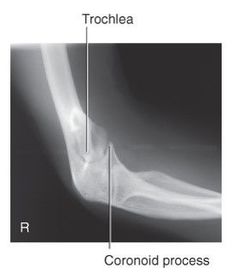

Which elbow projection/position best demonstrates the coronoid process? AP Oblique - medial rotation

AP Oblique Medial (Internal) Rotation 60-75 kVp 40 SID 10x12 IR nongrid CR @ midelbow joint MUST SEE coronoid process, trochlea, and medial epicondyle

Which oblique elbow projection best demonstrates the coronoid process? AP Oblique projection - Medial rotation

What anatomy is in profile for a medial oblique elbow? trochlea coronoid semilunar notch